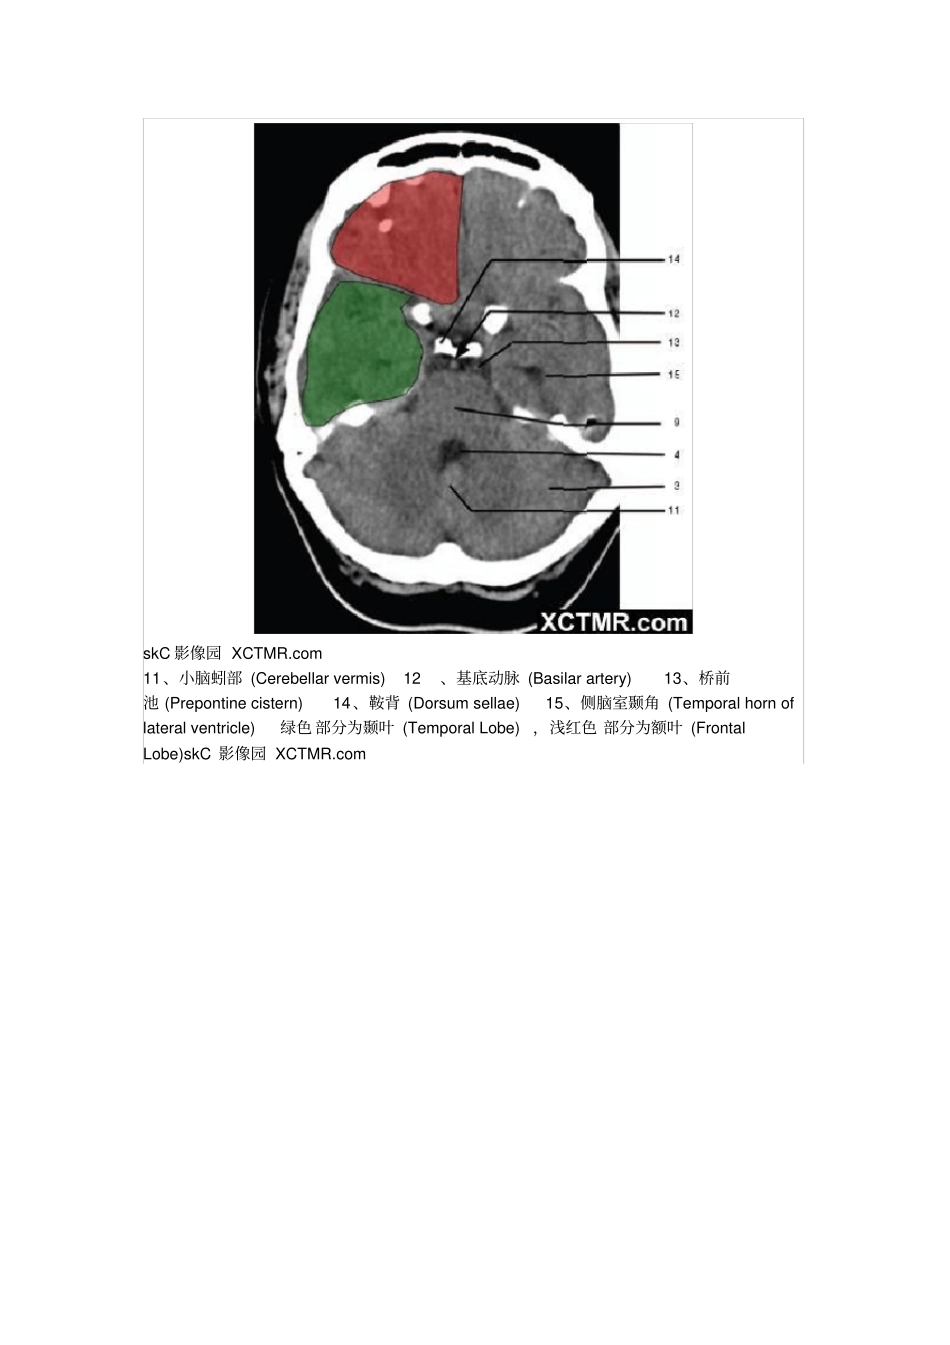

颅脑CT解剖(图文)skC影像园XCTMR.com1、蝶窦(Sphenoidsinus)2、延髓(Medullaoblongata)3、小脑(cerebellum)绿色部分为颞叶(TemporalLobe),浅红色部分为额叶(FrontalLobe)skC影像园XCTMR.comskC影像园XCTMR.comskC影像园XCTMR.com4、第四脑室(Fourthventricle)5、小脑中角(Middlecerebellarpeduncle)6、乙状窦(Sigmoidsinus)7、颞骨及乳突气房(Petroustemporalboneandmastoidaircells)8、桥小脑角(Cerebellopontineangle)9、脑桥(Pons)10、垂体窝(Pituitaryfossa)绿色部分为颞叶(TemporalLobe),浅红色部分为额叶(FrontalLobe)skC影像园XCTMR.comskC影像园XCTMR.com11、小脑蚓部(Cerebellarvermis)12、基底动脉(Basilarartery)13、桥前池(Prepontinecistern)14、鞍背(Dorsumsellae)15、侧脑室颞角(Temporalhornoflateralventricle)绿色部分为颞叶(TemporalLobe),浅红色部分为额叶(FrontalLobe)skC影像园XCTMR.comskC影像园XCTMR.com16、环池(Ambientcistern)17、角间池(Interpeduncularcistern)18、大脑角(Cerebralpeduncle)19、侧裂池(Sylvianfissure)绿色部分为颞叶(TemporalLobe),浅红色部分为额叶(FrontalLobe)skC影像园XCTMR.comskC影像园XCTMR.com20、小脑上池(Thirdventricle)21、侧脑室前角(Frontalhornoflateralventricle)21a、第三脑室(Thirdventricle)绿色部分为颞叶(TemporalLobe),浅红色部分为额叶(FrontalLobe),黄色部分为枕叶(OccipitalLobe)skC影像园XCTMR.comskC影像园XCTMR.com22、尾状核头部(Headofcaudatenucleus)23、岛叶(Insularcortex)24、外囊(Externalcapsule)25、豆状核(Lentiformnucleus)26、丘脑(Thalamus)绿色部分为颞叶(TemporalLobe),浅红色部分为额叶(FrontalLobe),黄色部分为枕叶(OccipitalLobe)skC影像园XCTMR.comskC影像园XCTMR.com27、纵裂(Interhemisphericfissure)28、内囊前肢(Anteriorlimbofinternalcapsule)29、内囊膝部(Genuofinternalcapsule)30、内囊后肢(Posteriorlimbofinternalcapsule)31、侧脑室三角区及脉络丛钙化(Trigoneoflateralventricleandcalcifiedchoroidplexus)32、侧脑室枕角(Occipitalhornoflateralventricle)绿色部分为颞叶(TemporalLobe),浅红色部分为额叶(FrontalLobe),黄色部分为枕叶(OccipitalLobe),褐色部分为顶叶(ParietalLobe)skC影像园XCTMR.comskC影像园XCTMR.com33、侧脑室体部(Bodyoflateralventricle)34、放射冠(Coronaradiata)浅红色部分为额叶(FrontalLobe),黄色部分为枕叶(OccipitalLobe),褐色部分为顶叶(ParietalLobe)skC影像园XCTMR.comskC影像园XCTMR.com35、半卵圆中心(Centrumsemiovale)浅红色部分为额叶(FrontalLobe),黄色部分为枕叶(OccipitalLobe),褐色部分为顶叶(ParietalLobe)额骨(FB—Frontalbone)顶骨(PB—Parietalbone)枕骨(OB—Occipitalbone)skC影像园XCTMR.comskC影像园XCTMR.com36、中央前回(Pre-centralgyrus)37、中央沟(Centralsulcus)38、中央后回(Post-centralgyrus)浅红色部分为额叶(FrontalLobe),褐色部分为顶叶(ParietalLobe)skC影像园XCTMR.comskC影像园XCTMR.com浅红色部分为额叶(FrontalLobe),褐色部分为顶叶(ParietalLobe)skC影像园XCTMR.comskC影像园XCTMR.com浅红色部分为额叶(FrontalLobe),褐色部分为顶叶(ParietalLobe)skC影像园XCTMR.com